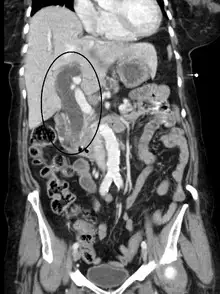

Biliary tract dilation due to obstruction as seen on CT scan (sagittal plane)

Most people presenting with jaundice will have various predictable patterns of liver panel abnormalities, though significant variation does exist. The typical liver panel will include blood levels of enzymes found primarily from the liver, such as the aminotransferases (ALT, AST), and alkaline phosphatase (ALP); bilirubin (which causes the jaundice); and protein levels, specifically, total protein and albumin. Other primary lab tests for liver function include gamma glutamyl transpeptidase (GGT) and prothrombin time (PT).[28] No single test can differentiate between various classifications of jaundice. A combination of liver function tests as well as other physical examination findings is essential to arrive at a diagnosis.[29]

Medical imaging such as ultrasound, CT scan, and HIDA scans are useful for detecting bile duct blockage.[32]